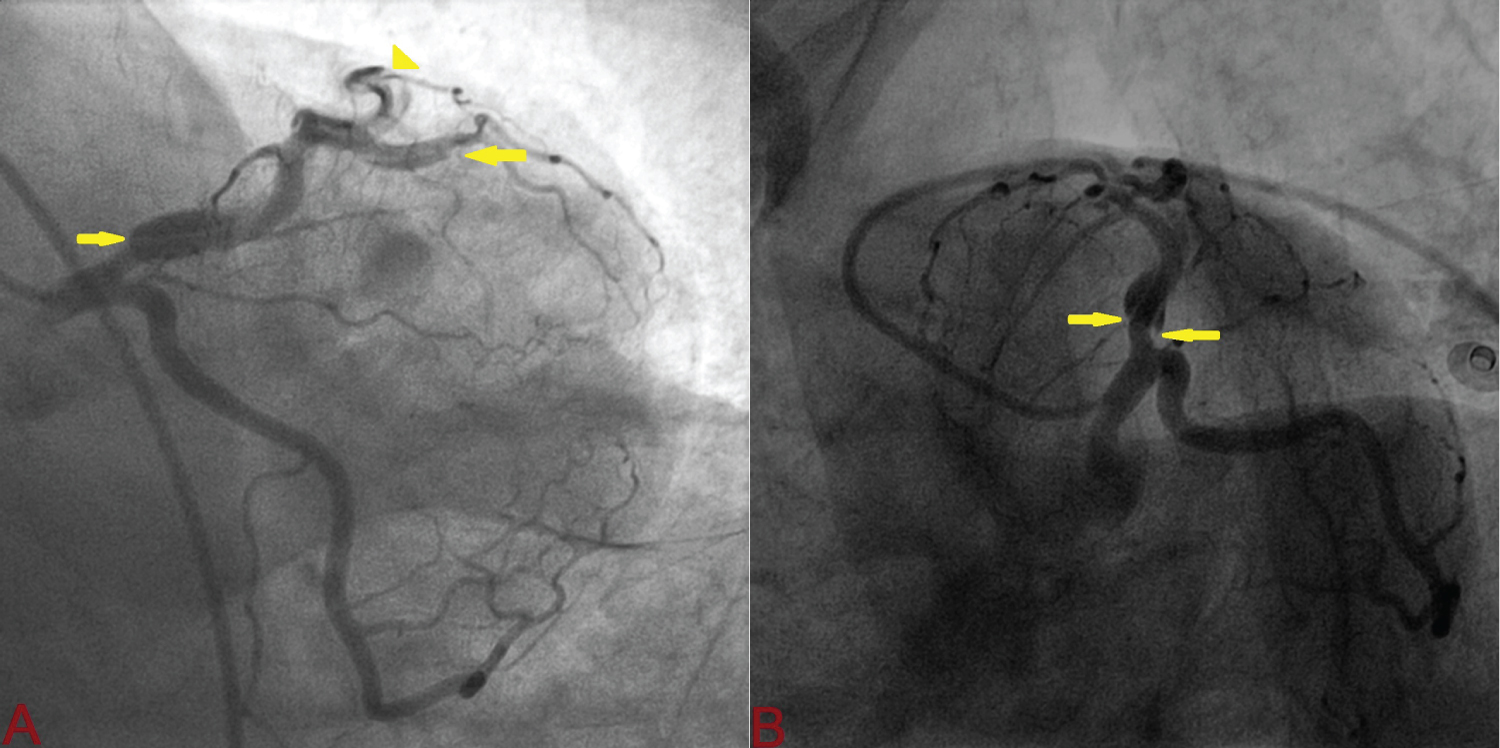

A 32-year-old apparently healthy male presented with excruciating chest pain with diaphoresis of 2-hour duration. His pulse rate was 85 beats/min and blood pressure was 110/84 mmHg. Other physical findings were all normal. Electrocardiogram showed normal sinus rhythm and ST-elevation in V1-V6 with reciprocal changes in inferior leads. An echocardiogram revealed regional wall motion abnormality in left anterior descending artery territory (LAD) with mild left ventricular (LV) systolic dysfunction (ejection fraction = 45%). His routine blood examinations were normal. He was loaded with aspirin 300 mg, clopidogrel 300 mg and thrombolysed with 40 mg Tenecteplase. At 90 minute, chest pain was persistent with little resolution of ST segment (≤ 50% from initial elevation) which indicated failed lyses. Coronary angiography was performed through transfemoral after obtaining written consent. LAD showed large, spontaneous spiral dissection with flap beginning from osteo-proximal segment extending up to mid segment involving first diagonal branch which was labelled as Type-D SCAD (Figure 1 and Figure 2). As the origin of dissection flap was appreciated on first injection and originating away from the ostial segment of LAD, it ruled out iatrogenic dissection. The rest of his coronary trees were normal. PCI was advised PCI but patient refused. He was conservatively managed with Ecospirin 75 mg, Clopidogrel 75 mg, Rosuvastatin 10 mg, Ramipril 5 mg and Metoprolol 100 mg. Repeat angiogram 4-weeks later revealed complete healing of dissection along with borderline lesion (Figure 3). Echocardiography indicated normalization of systolic function (ejection fraction-70%). As his treadmill test was negative for exercise induced myocardial ischaemia, he was managed conservatively.

Figure 3: Complete sealing of intimal flap (A: Antero-posterior caudal view; B: Spider oblique caudal view. Green arrow indicate sealed flap). View Figure 3